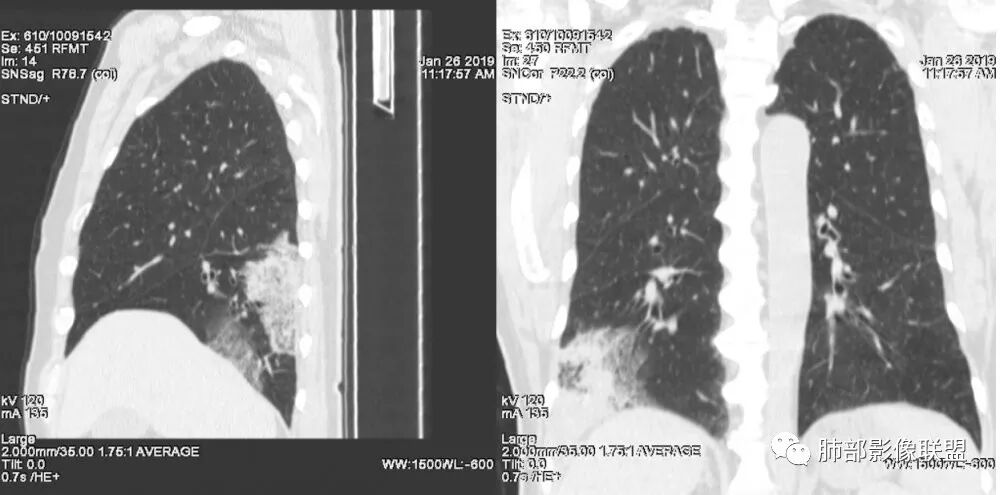

老年女性,右肺下叶沿胸膜下大片状高密度影,外周磨玻璃影,边界较清,内可见蜂窝征及支气管充气征,考虑肺炎型肺癌。

老年女性,咳嗽咳痰病史,右肺下叶大片磨玻璃实变影,胸膜下分布,支气管进入后扩张、僵直,磨玻璃影边界清楚,考虑粘液腺癌。鉴别肺炎。

右肺下叶基底段靠胸膜实变/磨玻璃混杂密度影,边界清楚,内见多发空泡(蜂窝样趋势改变?); 临床:咳嗽咳痰,无发热、胸痛; 考虑腺癌:无发热,感染性病变不首先考虑;部分层面形态类楔形,鉴别肺栓塞

老年女性,右下肺实变影,病灶里有小叶内间质增厚,周围GGo,支气管扩张,粘液性腺癌?淋巴瘤?

中年女性,咳嗽咳痰。右肺下叶片状高密度影,部分实性密度,周围见边界清晰磨玻璃影,内见小空泡,实性区部分支气管堵塞,有重力效应,考虑肺炎型肺癌,建议查痰脱落细胞。

老年人,右肺下叶斑片状阴影,病灶有膨胀性,边缘可见磨玻璃影,其边界清晰,内见僵硬的支气管,部分支气管扩张,首先考虑占位性病变,粘液性腺癌可能。鉴别感染性病变,后者边缘多有收缩性改变或者平直,内部支气管走形自然。

中年女性,右肺下叶沿胸膜下大片状高密度影,实变加GGO,外朝内发展,边界较清,内可见蜂窝征及枯树征,考虑肺炎型肺癌。

右肺病灶,病灶较大,实性+周边ggo,边界清晰,胸膜下分布,长轴平行于胸膜,内部支气管充气征,因不发热,暂不考虑感染性病变,支持肺炎型肺癌。

女性,咳嗽咳痰不发烧,右下外基底段实变影,边缘清楚GGO,有充气支气管征,枯树枝不明显,由外向内;诊断:肺炎型肺腺癌;鉴别:1、肺栓塞(外型神似,但无胸痛丶咯血);2丶肺炎

老年女性,右下肺实变影,糊墙,外朝内发展,病灶里有小叶内间质增厚,周围边界清楚了GGO,支气管扩张明显,考虑粘液癌;不符合点,支气管扩张太厉害了,鉴别淋巴瘤。

患者中年女性,咳嗽咳痰就诊。胸部CT:右肺下叶后基底段片状实变影,由胸膜向内发展呈扇形,病灶里有小叶内间质增厚、蜂窝状影,周围边界清楚GGO,内可见扩张支气管,淋巴结无明显肿大。综合符合粘液腺癌。

老年女性;右下肺混合实变影,呈楔形改变,边缘清晰,支气管进入且扩张,蜂窝状改变,考虑粘膜相关淋巴瘤,鉴别粘液腺癌,肺栓塞。

女,55咳嗽咳痰,右肺下叶片状实变,磨玻璃影及蜂窝影,考虑粘液腺癌。

老年女性,咳嗽、咳痰。右肺下叶沿胸膜下大片状高密度影,外周磨玻璃影,边界较清,小空泡,蜂窝征及支气管充气征,叶间裂串珠征,考虑:肺炎型肺癌,鉴别:肺克,链球菌,NTM等感染。

右肺下叶大片状影,密度不均匀,部分实变部分磨玻璃,大部分病灶尚清晰,其内支气管稍扩张,中年女性,首先考虑粘液腺癌,待鉴别淋巴瘤,常规抗炎治疗后复查。

中年女性,右肺下叶实变,近似扇形,外朝内发展趋势,外围紧贴胸膜面,中心密度略高,边缘密度略低,病灶内支气管略扩张。考虑肺炎型肺癌。常规建议抗炎治疗后复查,如无变化或变化不明显,建议穿刺活检。

胸膜下,实变,毛玻璃影,囊,边界清,枯枝,粘液腺。

老年女性,右肺下叶大片实变,小叶间隔及小叶内间隔增厚,边界较清,其内支气管似乎可见稍扭曲,分支减少。考虑1.肺炎型肺癌2.结合临床除外类脂性肺炎。

起源于胸膜下,实性成分,边缘Ggo,边界清晰,内可见小叶间隔增厚,粘液腺癌可能。建议先消炎后复查。

右肺下叶胸膜下大片状MGGO,其内结构紊乱,可见空泡征,病灶内近端支气管扩张,远端闭塞,形态不规则,边界部分清楚,部分似清非清,考虑粘液腺癌,鉴别淋巴瘤

该病灶主病灶位于胸膜下(肋膈角处),边缘膨隆改变,周围毛玻璃,边界清楚,病灶内支气管僵直,轻度扩张,小分支无,符合枯树枝改变,有多发小空泡(难与支气管区别),应该符合肺炎性肺癌,但无蜂窝,没有增强无法判断有无粘液、血管特点,如果周围显示的空泡是支气管,其已达到远端,这些有符合炎性特点,工作中,我会先抗炎膨后复查再定。

这是潘老师说的外向内吗?右下实变,蜂窝,GGO,支气管变形迂曲,局部膨胀感,肺炎性肺癌,粘液腺癌可能。常规先抗炎再复查。鉴别淋巴瘤,淋巴瘤支气管一般不变形,壁光整,病程长。

1.本例病灶较大片混杂密度影,胸膜下分布为主(未沿着支气管分布),该分布特点可见于大叶性肺炎、干酪性肺炎、淋巴瘤及粘液腺癌等。可惜未提供增强扫描图像。

2.病灶示中央实变区,周围GGO,可见明显小叶间隔增厚,GGO边界清楚,应当考虑到恶性病变的可能性。肺炎因炎性水肿及渗出,影像上边界常模糊不清,注意早期粘液腺癌可出现似清非清的边界。粘液腺癌因粘液成份较多,密度一般偏低,纵隔窗病灶常会消隐或范围会明显缩小,这不同于炎性实变。

3.病灶内支气管走形略显僵直,侧支少(粘液阻塞),也符合肺腺癌的枯树枝征。而大叶性肺炎的支气管是管壁光整、通畅、自然,结核的支气管常常壁增厚,甚至狭窄后扩张;

4.患者临床症状不重,临床炎性指标不高,结合肺内影像,应警惕肺炎型肺癌。